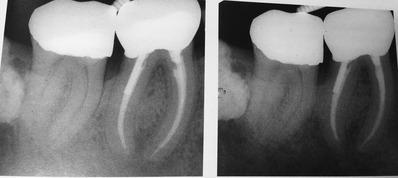

¥×¥é¡¼¥¯¥³¥ó¥È¥í¡¼¥ë¤Î¼£ÎÅÃæ¤Ç¤¹¡£